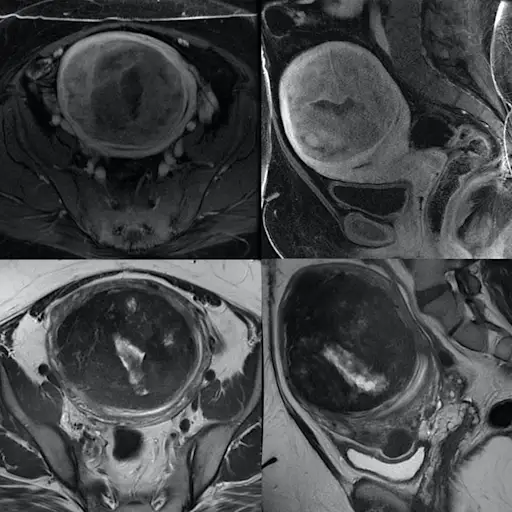

子宫肌瘤的诊断

总体而言,根据美国生殖医学学会的数据,5%至10%的努力孕妇的妇女患有肌瘤。巴尔的摩约翰·霍普金斯医学生殖科学与妇女健康研究部主任詹姆斯·塞加尔斯(James Segars,M.D.)说,第一个问题是诊断的延迟。On average, women wait 3.6 years before getting help, even after experiencing severe symptoms, and many don’t seek help at all because they think heavy bleeding, menstrual cramping, bloating, and bladder problems are nothing to worry about, according to a national survey in the美国妇产科杂志。

肌瘤位置影响生育能力

当涉及肌瘤所在的生育能力时,最大的不同。“肌瘤就像房地产一样。它的位置,位置,位置。” Segars博士说。医生定义子宫肌瘤,也称为Myomas或Leioymyomas,基于它们在您体内的位置:粘膜粘膜肌瘤发生在子宫腔衬里;壁内肌瘤位于子宫壁;并在子宫壁外发现了亚肠肌瘤。(注意:您可以拥有一个以上的肌瘤,并且可以在一个以上的位置。)

壁内肌瘤导致阻塞

塞加尔斯博士说,子宫壁可能会影响生育能力的另一种邪恶方式是阻止输卵管,但您可能没有意识到这一点。他说,如果有完全的障碍,那么怀孕的机会降至零。塞加尔斯博士说:“它们可以阻止一个或两个试管……这不一定可以在超声波上检测到。”要查看您的试管是否被肌瘤阻塞,您需要盐水超声图或滞后图(HSG),该过程使用放射性染料突出显示障碍物并检查正常流向子宫。

肌瘤大小如何影响生育能力

疯狂但真实:肌瘤可以从葡萄干(或较小)到西瓜的大小。大小可以在防止或破坏怀孕方面发挥作用,尤其是与位置有关。例如,据美国生殖医学学会称,直径大于6厘米的壁内肌瘤可能会干扰怀孕。但是,即使较小的肌瘤也会影响妊娠。塞加尔斯博士说:“这可能是半厘米,但是如果它是铃铛和毛衣(粘膜粘膜)肌瘤,它可以像宫内节育器一样。”